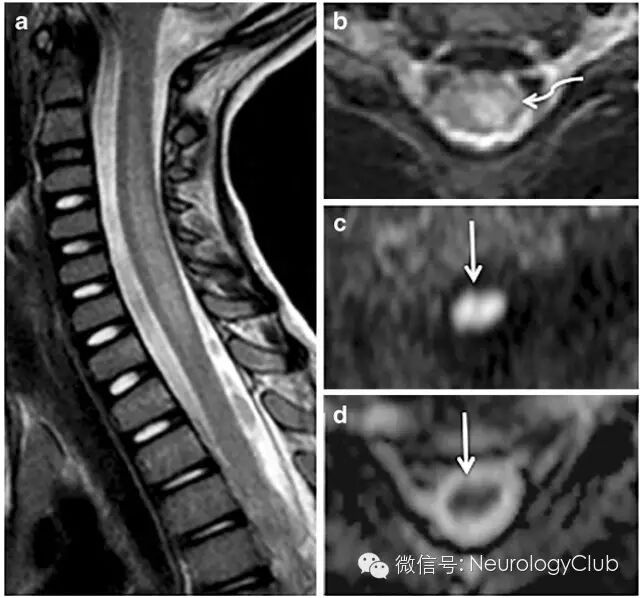

3干燥综合征

(a:C2-T2脊髓长节段T2高信号病灶;b:3天后复查;c:2周后复查;d:1.5年后复查,可见进行性脊髓萎缩)